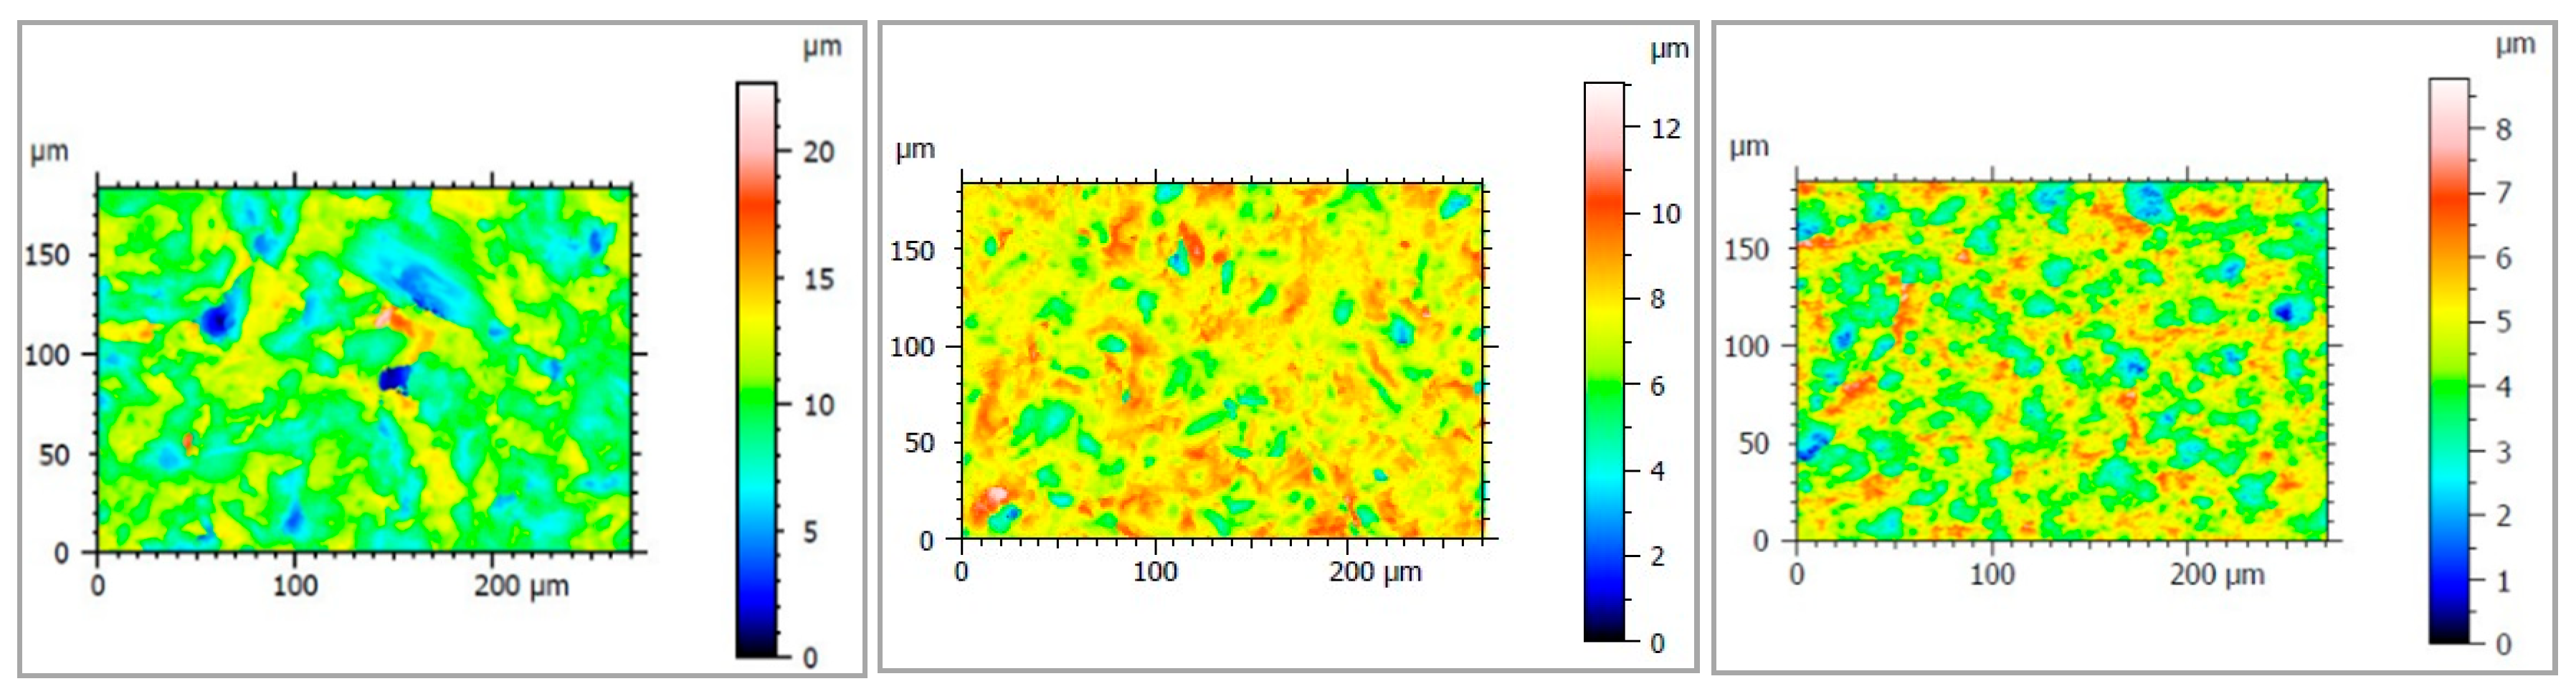

2.3. Cell Viability Study

3.2. Cell Viability Study